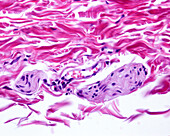

13613516 - Vein adventitia, light micrograph